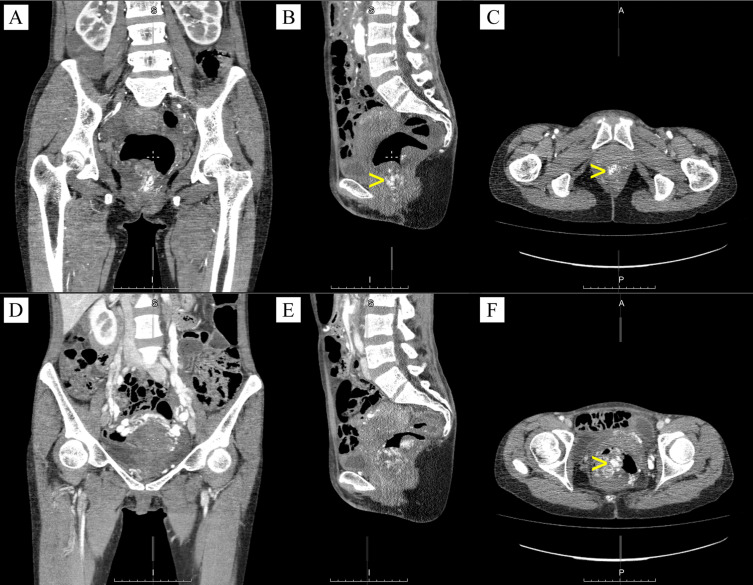

背景:直肠血管畸形与Klippel-Trenaunay综合征是非常罕见的。虽然他们的诊断可能是直截了当的特征,但由于其不寻常的表现和误诊的可能性,这些病例仍然具有重要的教育价值。病例介绍:我们的研究旨在描述一个45岁女性患者的临床病例。主诉有肛周疼痛,排便时/排便后周期性出血,痔疮脱垂,全身乏力。结肠镜检查显示直肠静脉曲张、直肠黏膜血管瘤和慢性内痔。对盆腔器官进行多层计算机断层扫描并静脉注射造影剂。临床初步诊断为直肠黏膜血管瘤,认为直肠血管畸形可手术。在我们的临床中,患者接受了几个阶段的手术:(1)在下腔静脉植入临时腔静脉过滤器,(2)两周后腹腔镜辅助直肠前切除术,预防性横结肠造口术和直肠粘膜脱粘术,(3)出院后7个月,关闭横结肠造口术。大体标本的病理检查显示,在切除远端延伸12.0 cm的部分,结肠粘膜致密,粗块状,颜色灰蓝色,有多个充血腔。术后进展顺利。第1天开始口腔营养和患者活动。术后创面初步愈合。患者于术后第6天顺利出院。结论:该病例定位罕见,病程长时间无症状,且有相当大的血管化过度的异常血管形成,值得关注。这种病理的合适方法是腹腔镜手术,这对于直肠血管畸形的诊断和根治性治疗都是有用的。

Case presentation: Our study aimed to describe a clinical case of a 45-year old female patient. There were complaints of pain in the perianal area and periodic bleeding during/after defecation, prolapse of hemorrhoids, general weakness. Colonoscopy revealed varicose veins of the rectum, hemangioma of the rectal mucosa, and chronic internal hemorrhoids. Multislice computed tomography of the pelvic organs with intravenous bolus contrast was performed. The preliminary clinical diagnosis was hemangioma of the rectal mucosa, and vascular malformation of the rectum was considered operable. In our clinic, the patient underwent several-stage surgery: (1) implantation of a temporary vena cava filter into the inferior vena cava, (2) two weeks later laparoscopic-assisted anterior resection of the rectum with preventive transverse colostomy and demucosation of the rectal mucosa, (3) after 7 months following discharge, the closure of transverse colostomy. Pathological examination of the gross specimen revealed that mucous membrane of the colon in a section extending 12.0 cm up to the distal edge of the resection is compacted, coarsely lumpy, grayish-bluish in color, with multiple blood-filled cavities. The postoperative period proceeded smoothly. Oral nutrition and patient's activity began on the 1st day. Primary healing of postoperative wounds was occurred. The patient was discharged in satisfactory condition on the 6th day post-surgery.